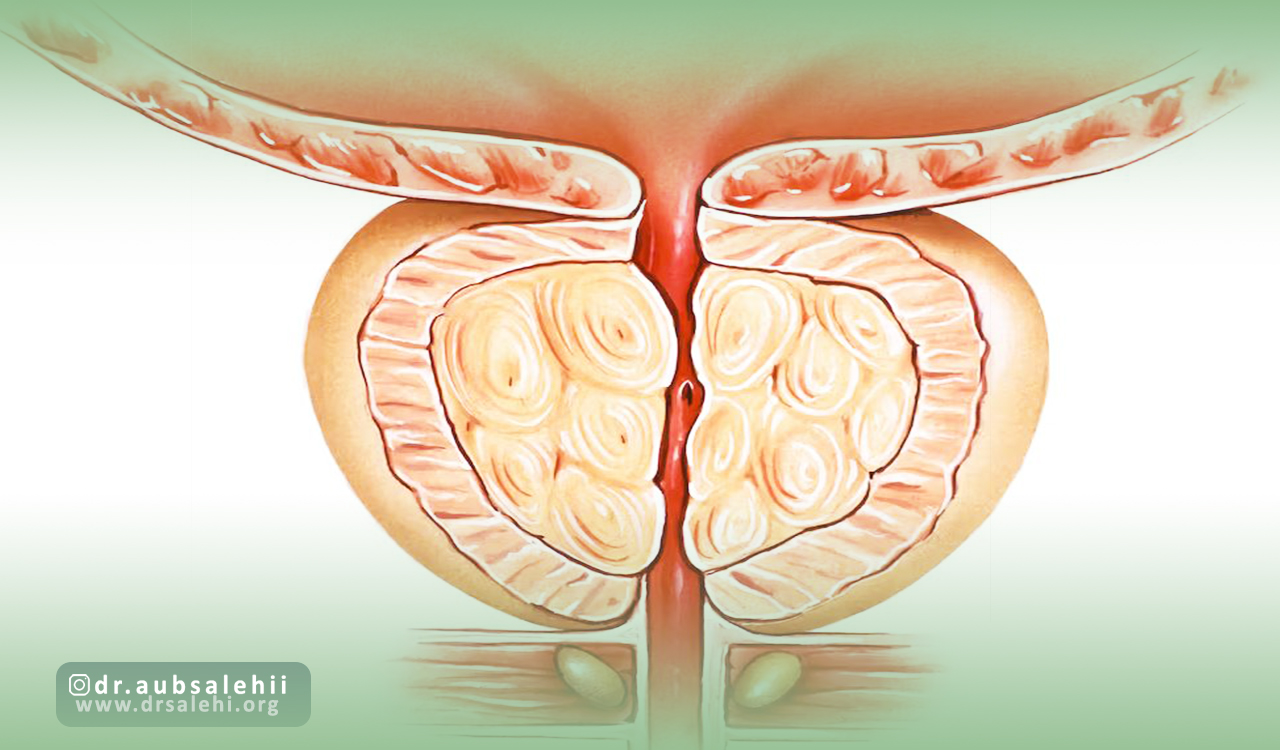

بزرگ شدن پروستات یکی از بزرگترین مشکلاتی است که ممکن است در سنین میانسالی به بعد برای آقایان اتفاق بیفتد.

اینکه چه دلیلی باعث بزرگی پروستات یا سرطان پروستات میشود در روند درمان آن بسیار مهم است.

در نتیجه این تغییرات با کمتر شدن جریان خون به پروستات کوچک تر شدن این غده اتفاق افتاده و علائم ادراری ناشی از بزرگی خوش خیم پروستات بهبود پیدا می کند.

به طور معمول کسانی که درگیر بزرگی پروستات هستند به مرور زمان مشکلات ادراری را هم تجربه می کنند.

این افراد با وجود تکرر ادرار، سختی در شروع ادرار یا جریان ضعیف ادرار با مشکلات بسیار زیادی مواجه خواهند شد که روند طبیعی زندگی آنها را مختل می کند.

آنژیوگرافی پروستات برای بیمارانی کاربرد دارد که درگیر بزرگی و رشد غیر عادی این غدد مهم هستند.

بزرگ شدن خوشخیم پروستات یا BPH یکی از شایعترین اختلالات پروستات در مردان مسن است.

این وضعیت باعث انسداد جریان ادرار و بروز علائمی مانند تکرر ادرار، سختی در شروع ادرار و شبادراری میشود.